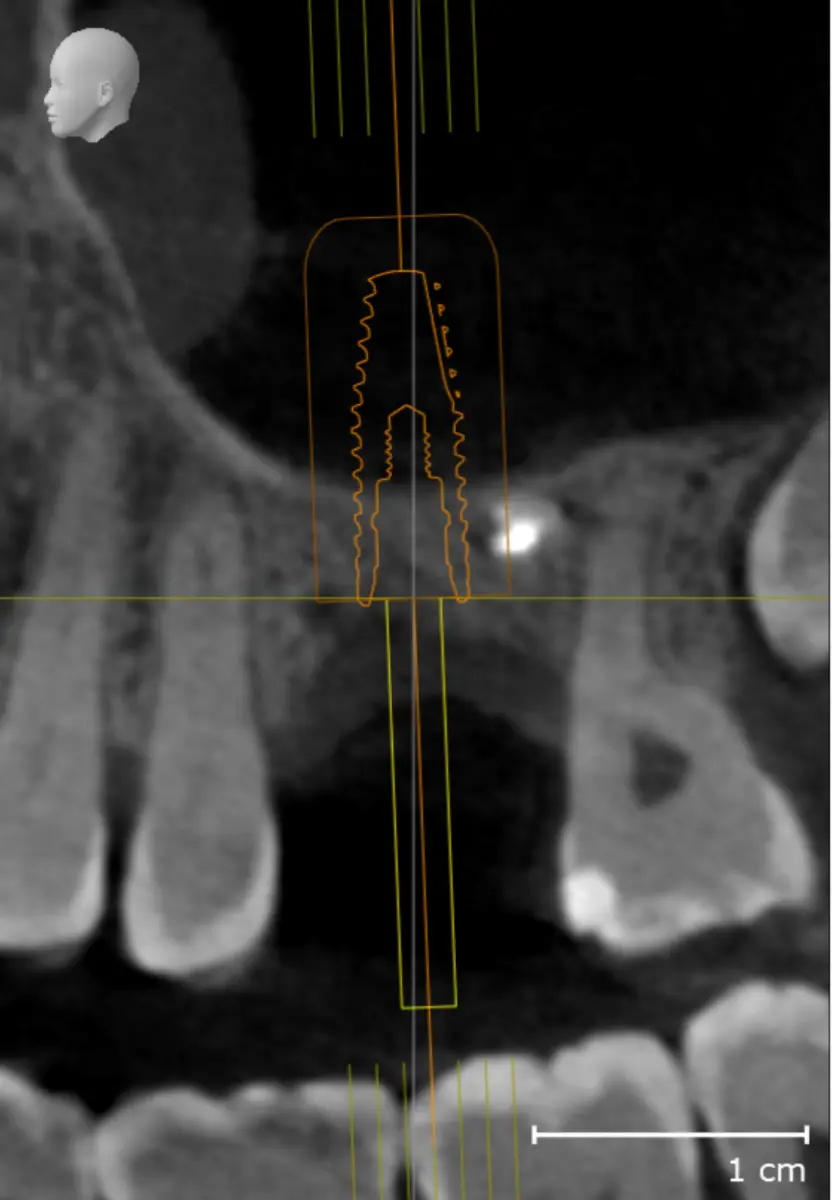

IMPLANTOLOGÍA

Siempre que el paciente reúna los requisitos clínicos adecuados, se irá con unas prótesis provisionales sobre los implantes que se colocarán en esa misma sesión.

La elevación de seno maxilar permite aumentar el hueso en la zona posterior del maxilar superior cuando no hay suficiente altura para colocar implantes. Al elevar el suelo del seno maxilar y añadir hueso autólogo o xenoinjerto, se consigue una base ósea sólida que garantiza la estabilidad y el éxito de los implantes dentales.